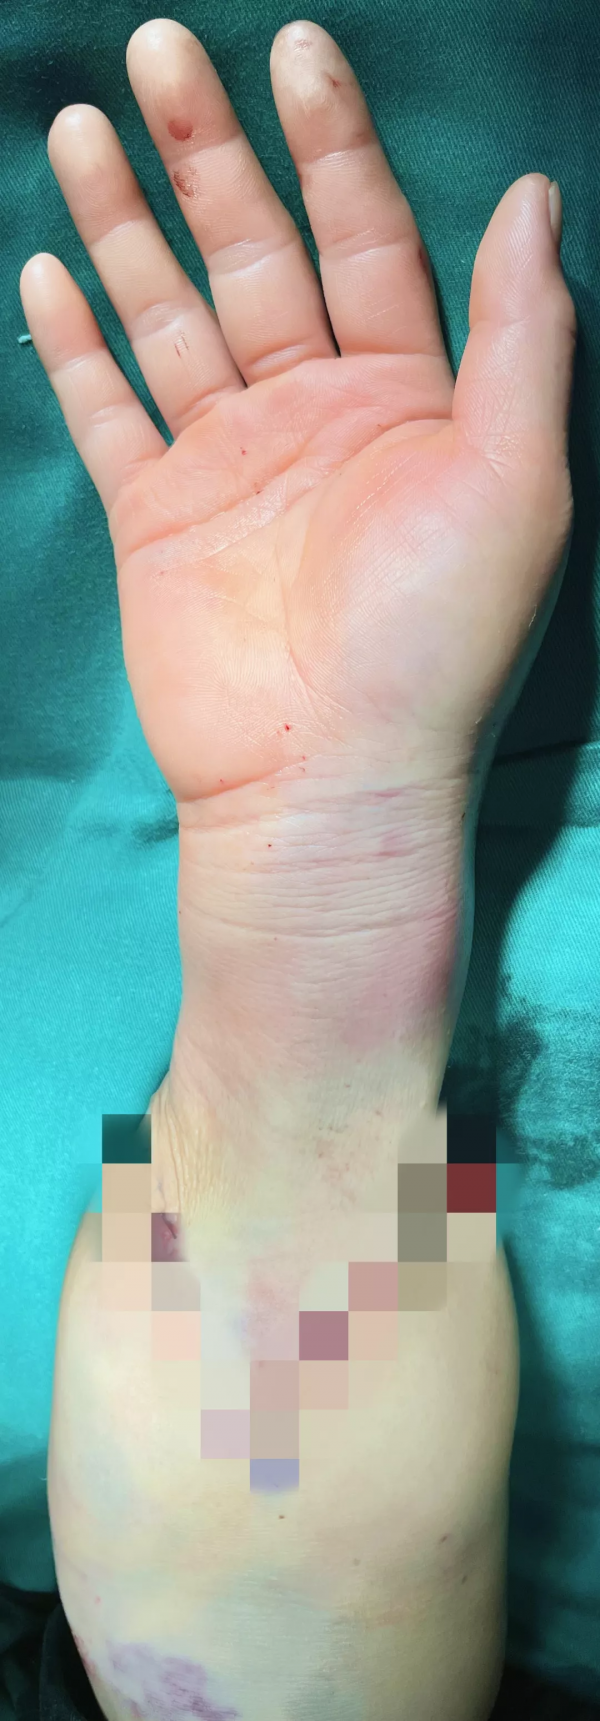

手外科及手術室麻醉科醫護團隊齊心協力, 6小時徹夜奮戰,為患者保住了右手。經過一日的優質護理,患者手指血運良好,精神恢復,臉上洋溢位久違的笑容。